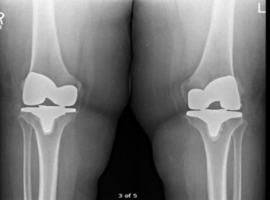

An Uncommon Complication: Common Peroneal Nerve Palsy After Medial TKA

Volume 4, Issue 4

Read More